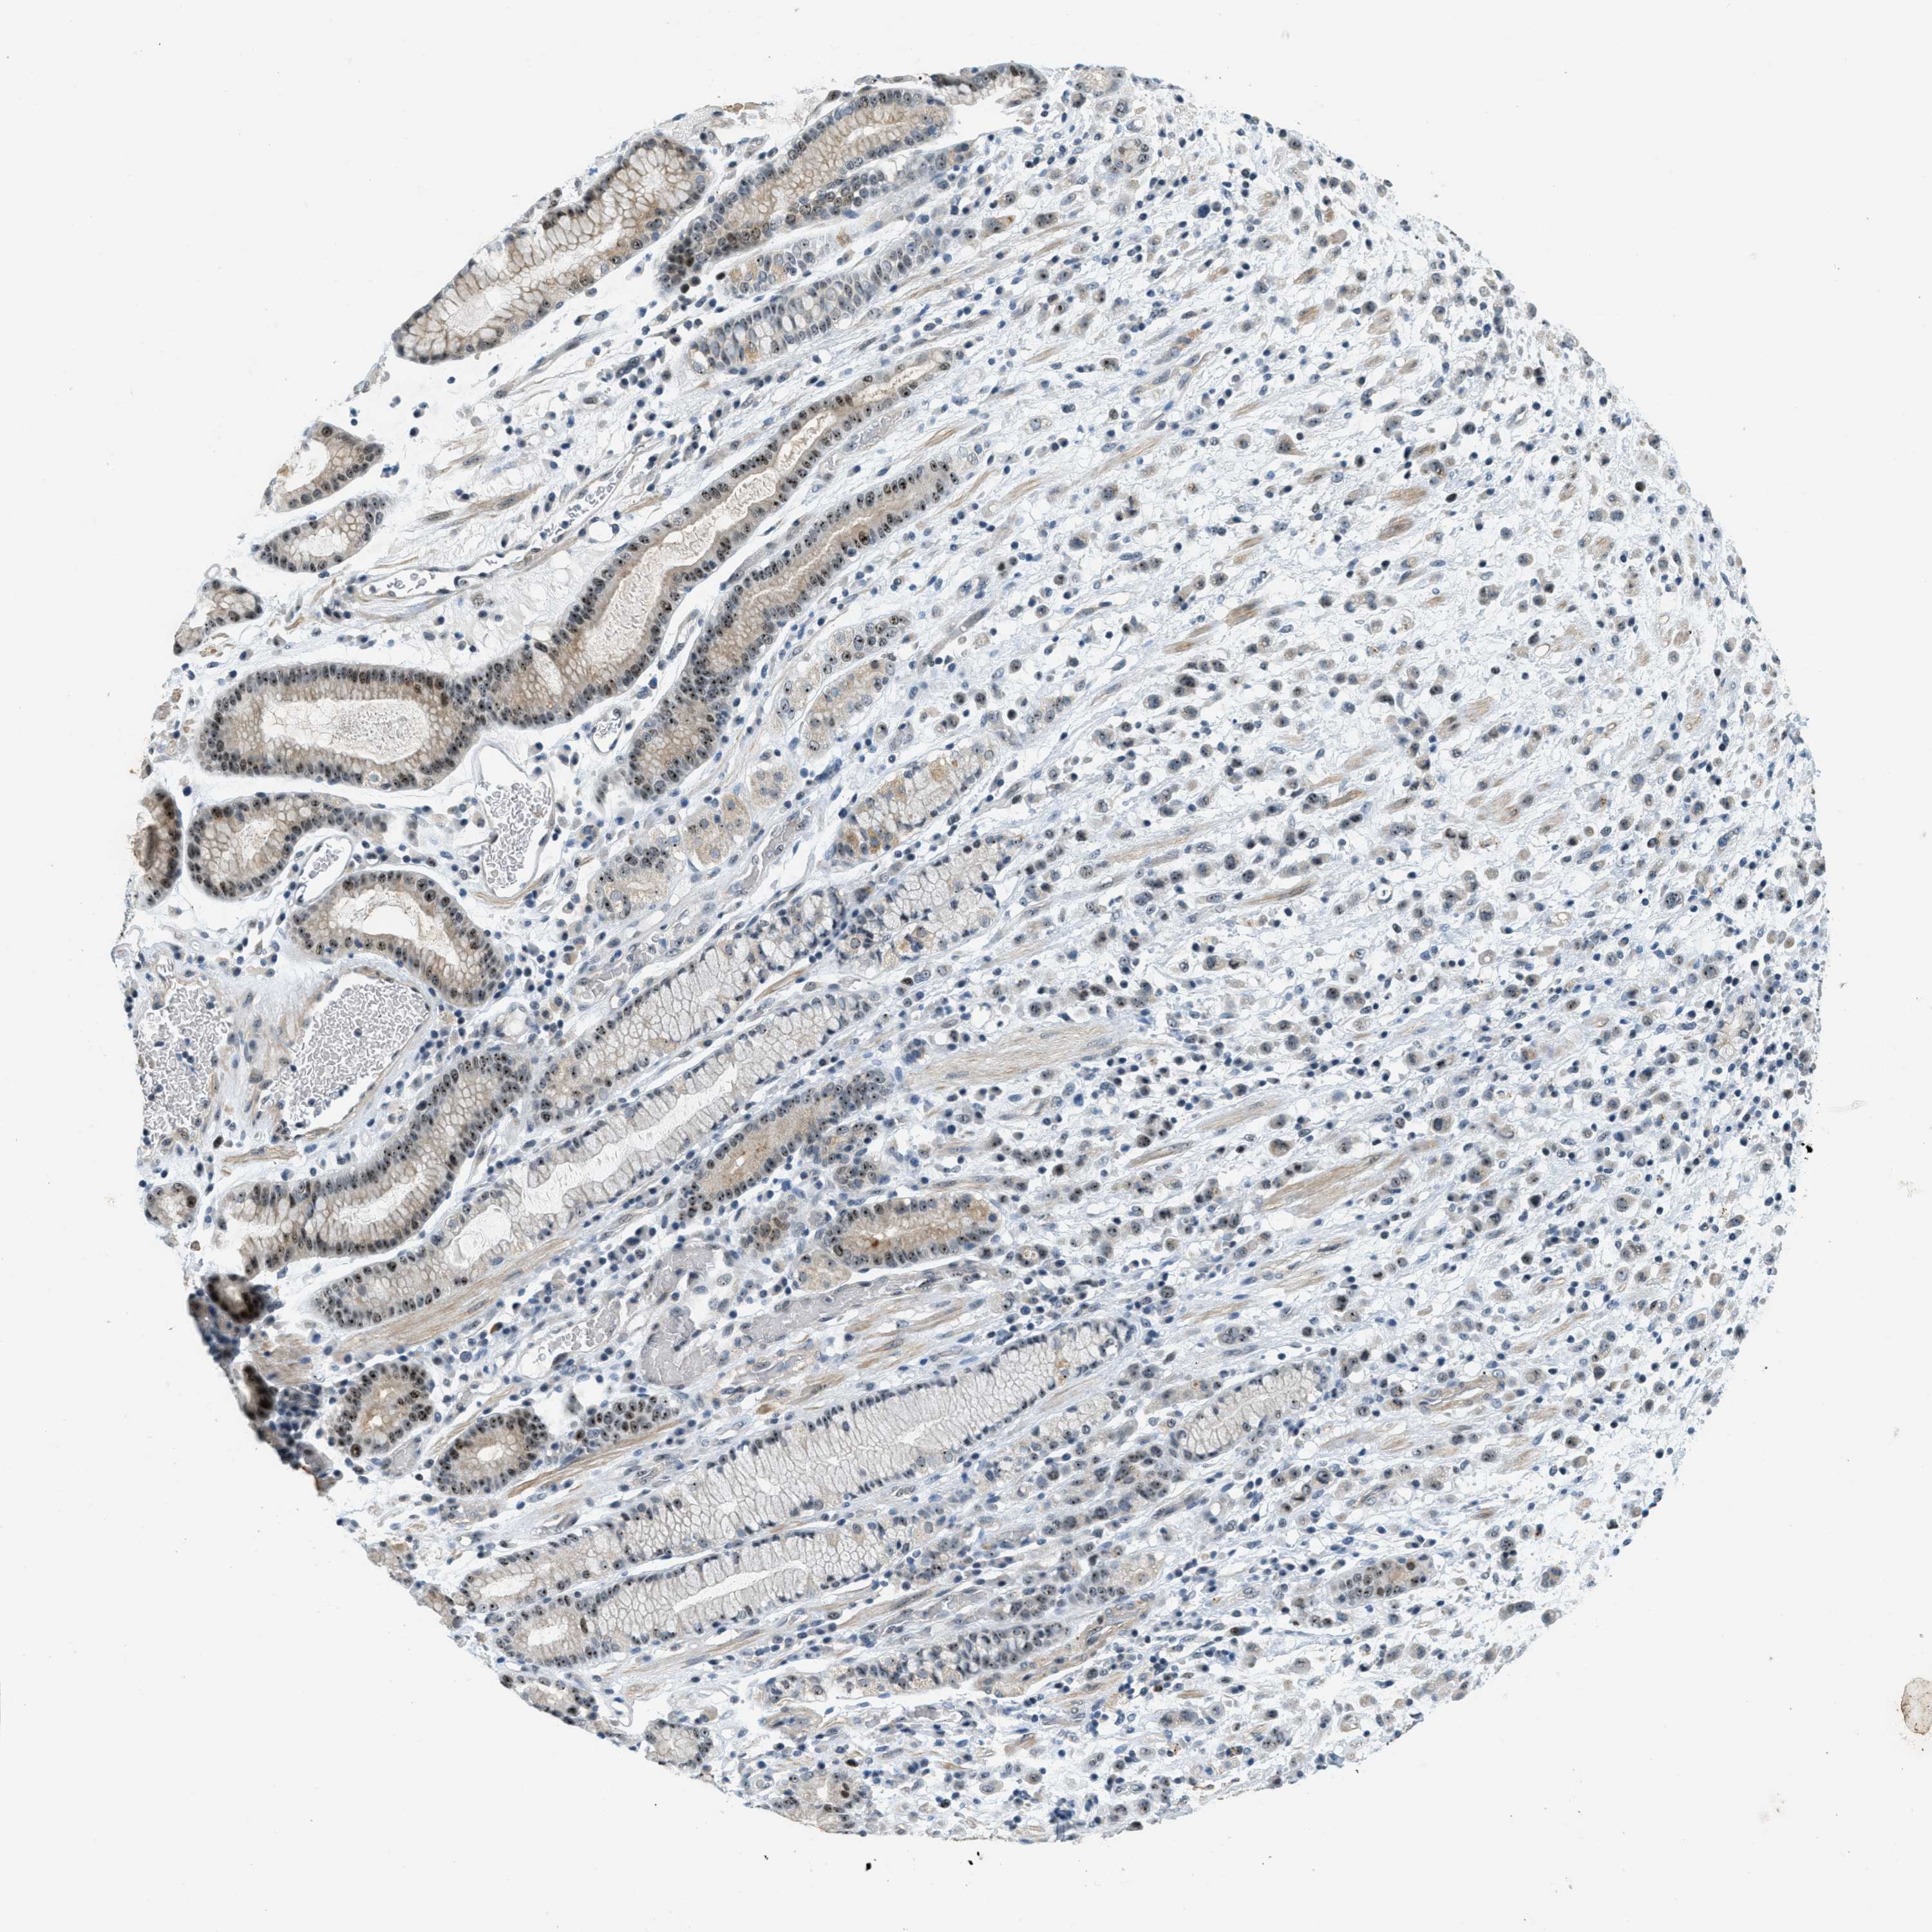

STOMACH CANCER - Protein expressioni

A mouse-over function shows sample information and annotation data. Click on an image to view it in a full screen mode. Samples can be filtered based on level of antibody staining by selecting one or several of the following categories: high, medium, low and not detected. The assay and annotation is described here.

Note that samples used for immunohistochemistry by the Human Protein Atlas do not correspond to samples in the TCGA dataset.

Antibody stainingi

Antibody staining in the annotated cell types in the current human tissue is reported as not detected, low, medium, or high, based on conventional immunohistochemistry profiling in selected tissues. This score is based on the combination of the staining intensity and fraction of stained cells.

Each image is clickable and will lead to virtual microscopy that enables deeper exploration of all samples and also displays staining intensity scores, fraction scores and subcellular localization as well as patient and tissue information for each sample.

Antibody HPA014855

Staining

High

Medium

Low

Not detected

Intensity

Strong

Moderate

Weak

Negative

Quantity

>75%

75%-25%

<25%

None

Location

Nuclear

Cytoplasmic/membranous

Cytoplasmic/membranous,nuclear

Adenocarcinoma, NOS